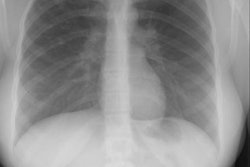

J Thorac Imaging 1992 Mar;7(2):62-77

Pulmonary involvement in collagen vascular disease: a review of the pulmonary manifestations of the Marfan syndrome, ankylosing spondylitis, Sjogren's syndrome, and relapsing polychondritis.

The pulmonary manifestations of collagen vascular diseases span an enormous

range of clinical and radiographic findings. The

breadth of these abnormalities is as diverse as the underlying diseases

themselves. A comprehensive discussion of pulmonary

involvement in four of these diseases, the Marfan syndrome, ankylosing

spondylitis, Sjogren's syndrome, and relapsing

polychondritis, is presented.